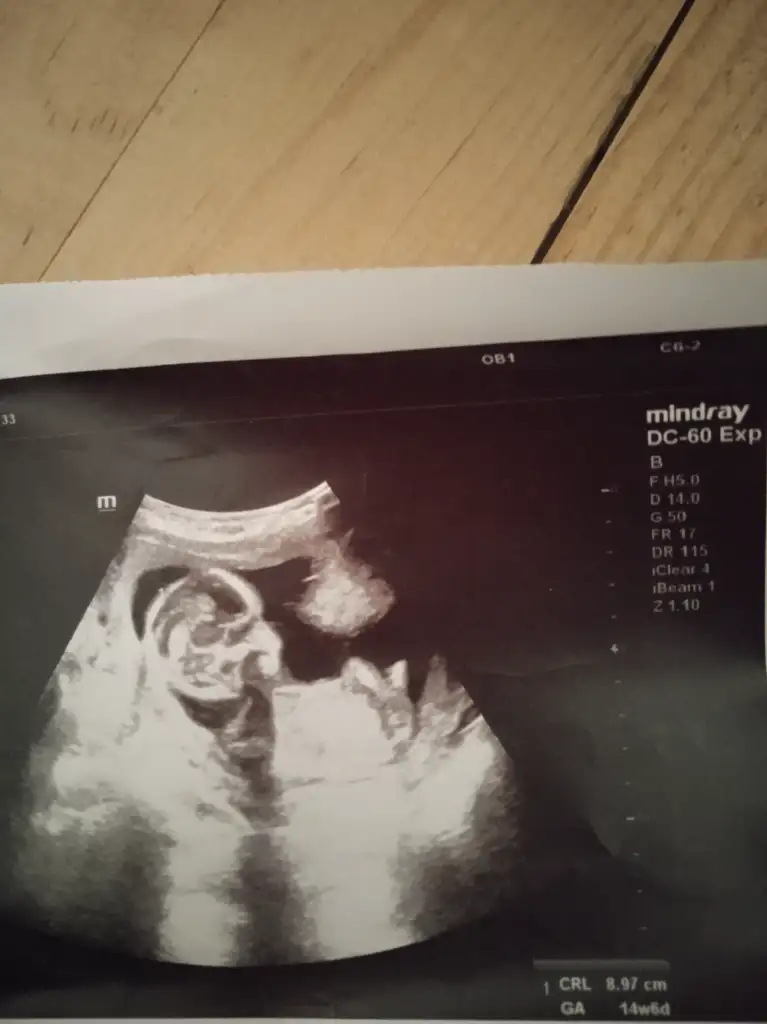

13+6 rica etsem bana da bakar mısınız

• IMG20250620181644.webp

17,4 KB · Görüntüleme: 41

• IMG20250620181647.webp

22,6 KB · Görüntüleme: 32